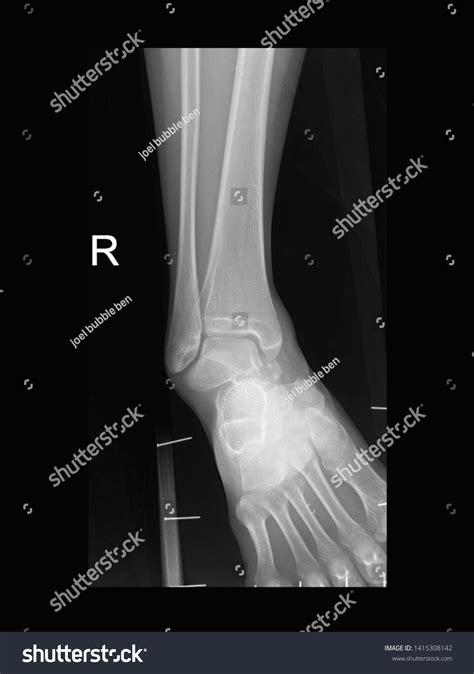

When you visit an urgent care clinic or an emergency room with ankle pain, the physician will first perform a physical examination. However, even the most experienced doctor cannot confirm a fracture just by looking at the surface. A broken ankle Xray is necessary to visualize the internal structure of the joint. It provides a clear, two-dimensional image of the tibia, fibula, and talus, allowing medical professionals to rule out or confirm a break.

• Positioning: You will be asked to sit or lie down on an examination table. The technician will position your ankle in three standard views: an anterior-posterior (front), lateral (side), and a mortise view (a slightly rotated view that better visualizes the joint space).